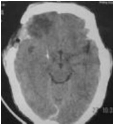

(3)医学核磁共振成像检查疾病。

(2)X光机透视拍照(图345)。头颅CT片(图346)。

图344 这车圆木多少立方

图346 头颅CT片